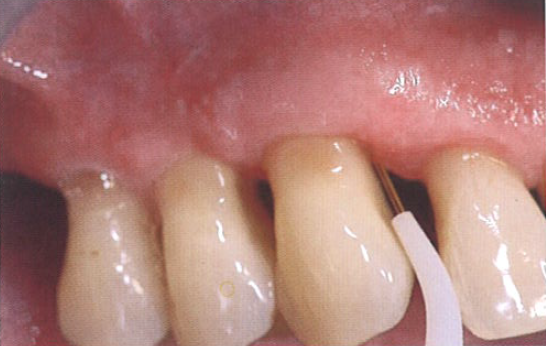

对于牙周炎治疗后的维护,其关键因素仍然是患者的家庭护理水平。医师必须抓住一切机会鼓励患者使用最合适的家庭护理方法。邻间隙宽大的情况不适合使用牙线,因为即使它能很好地清洁邻间隙,但并不适合清洁上颌前磨牙近中根面凹陷处的生物膜。在这种情况下,最好使用牙间隙刷,特别是一种具有特殊解剖形状的邻间隙刷(图12)。

图12  加强家庭护理技术,特别是对邻间隙的正常清洁至关重要